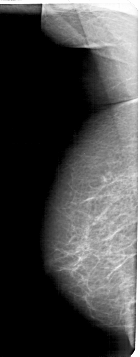

A_1600_1.LEFT_MLO

LEFT_MLO LINES 5341 PIXELS_PER_LINE 2086 BITS_PER_PIXEL 12 RESOLUTION 43.5 NON_OVERLAY